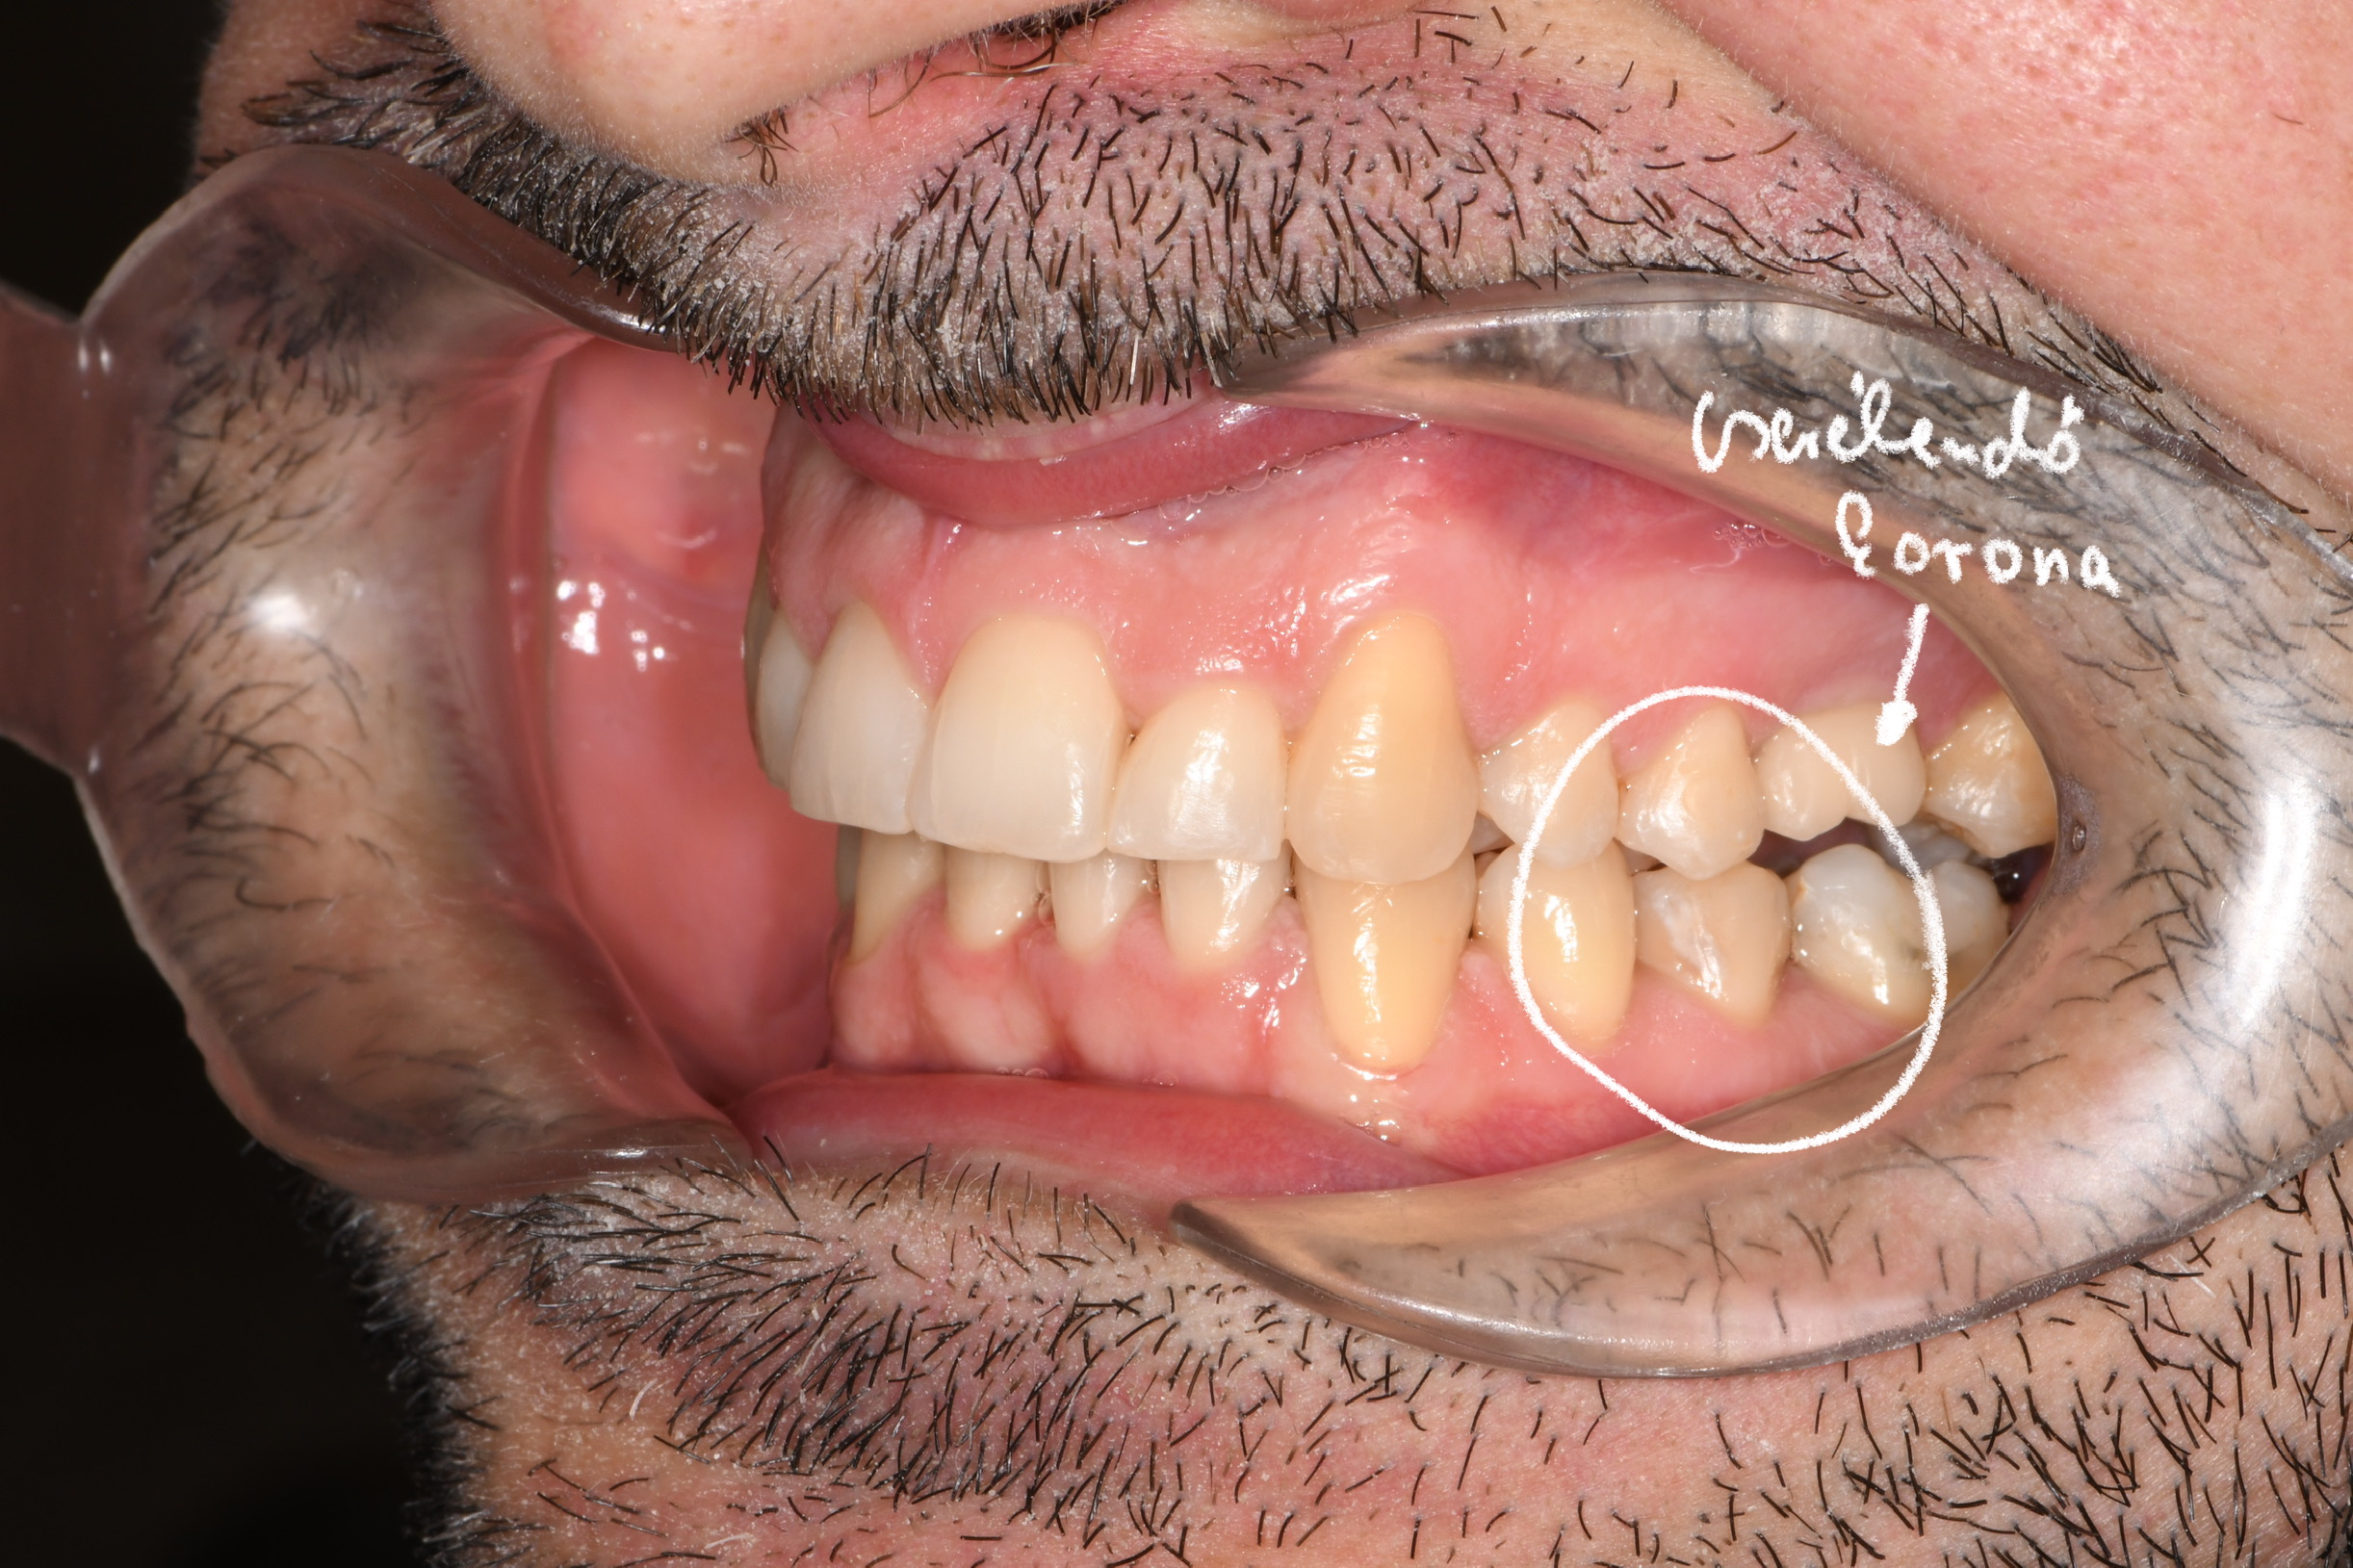

Az elmúlt évekből rengeteg szakmai referenciát tudnánk bemutatni, amelyek különböző fogszabályozási problémákat oldottak meg. Válogatva a több száz esetből, ezen az oldalon olyan képeket, információkat igyekeztünk bemutatni, amelyeknek a segítségével a jövőbeni pácienseinknek azt tudjuk üzenni: A Te fogsorod is lehet gyönyörű!

(Képeket a Pácienseink külön írásos beleegyezésével mutatjuk be!)